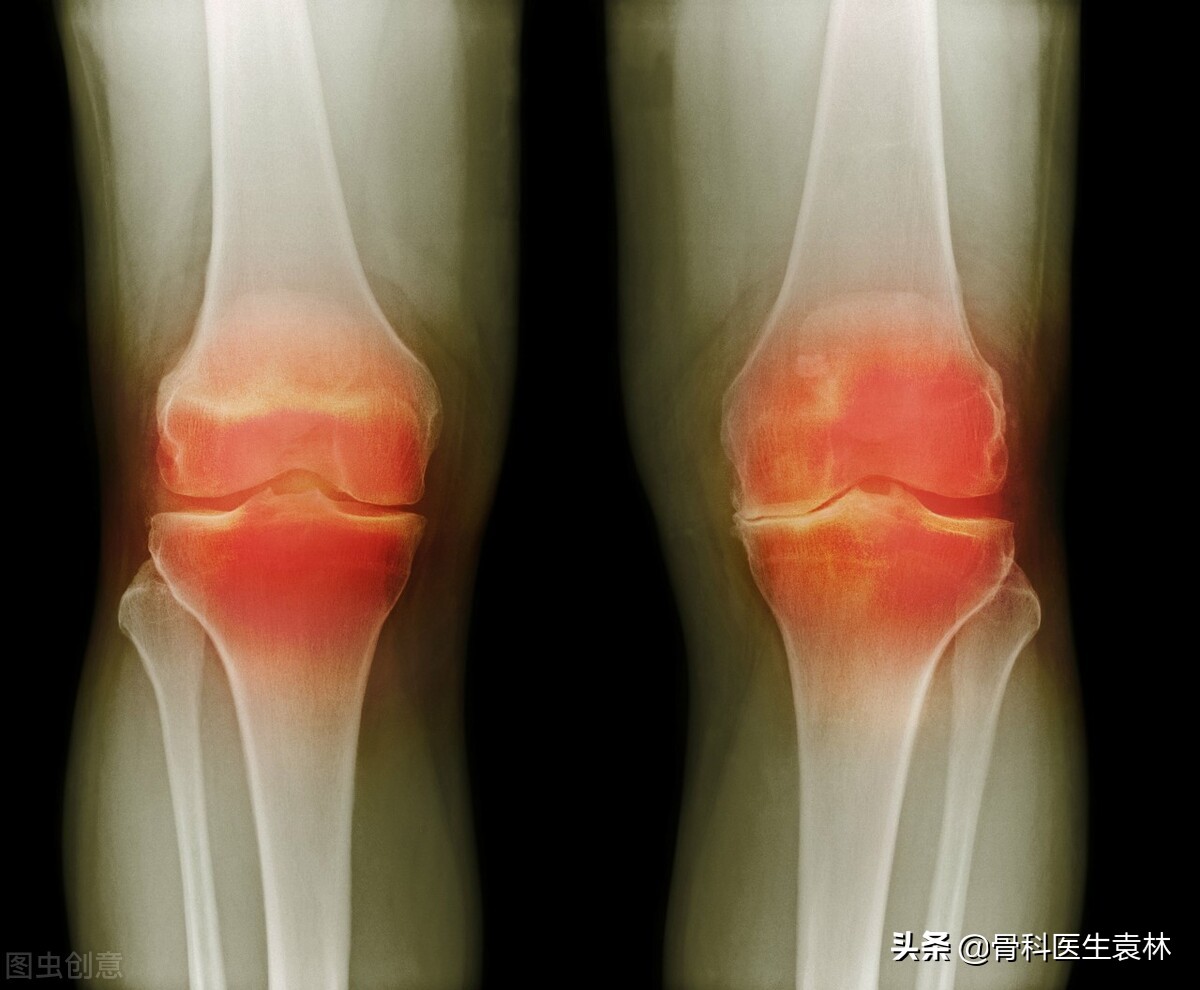

骨关节炎是骨科中非常常见的一种疾病,在生活中有很多人已经出现骨关节炎的早期的症状表现,有的患者的症状不是很严重,从而导致忽略了骨关节炎的严重性,可能大家在生活中经常的听说骨关节炎,但是有的人对骨关节炎的了解并不全面,今天我就给大家说一下,关节出现这5种情况,千万不要忽视了。

3、关节出现肿胀

关节肿胀是因局部的骨性肥大或渗出性滑膜炎引起,可伴局部温度增高、积液和滑膜肥厚,严重者可关节畸形、半脱位等。